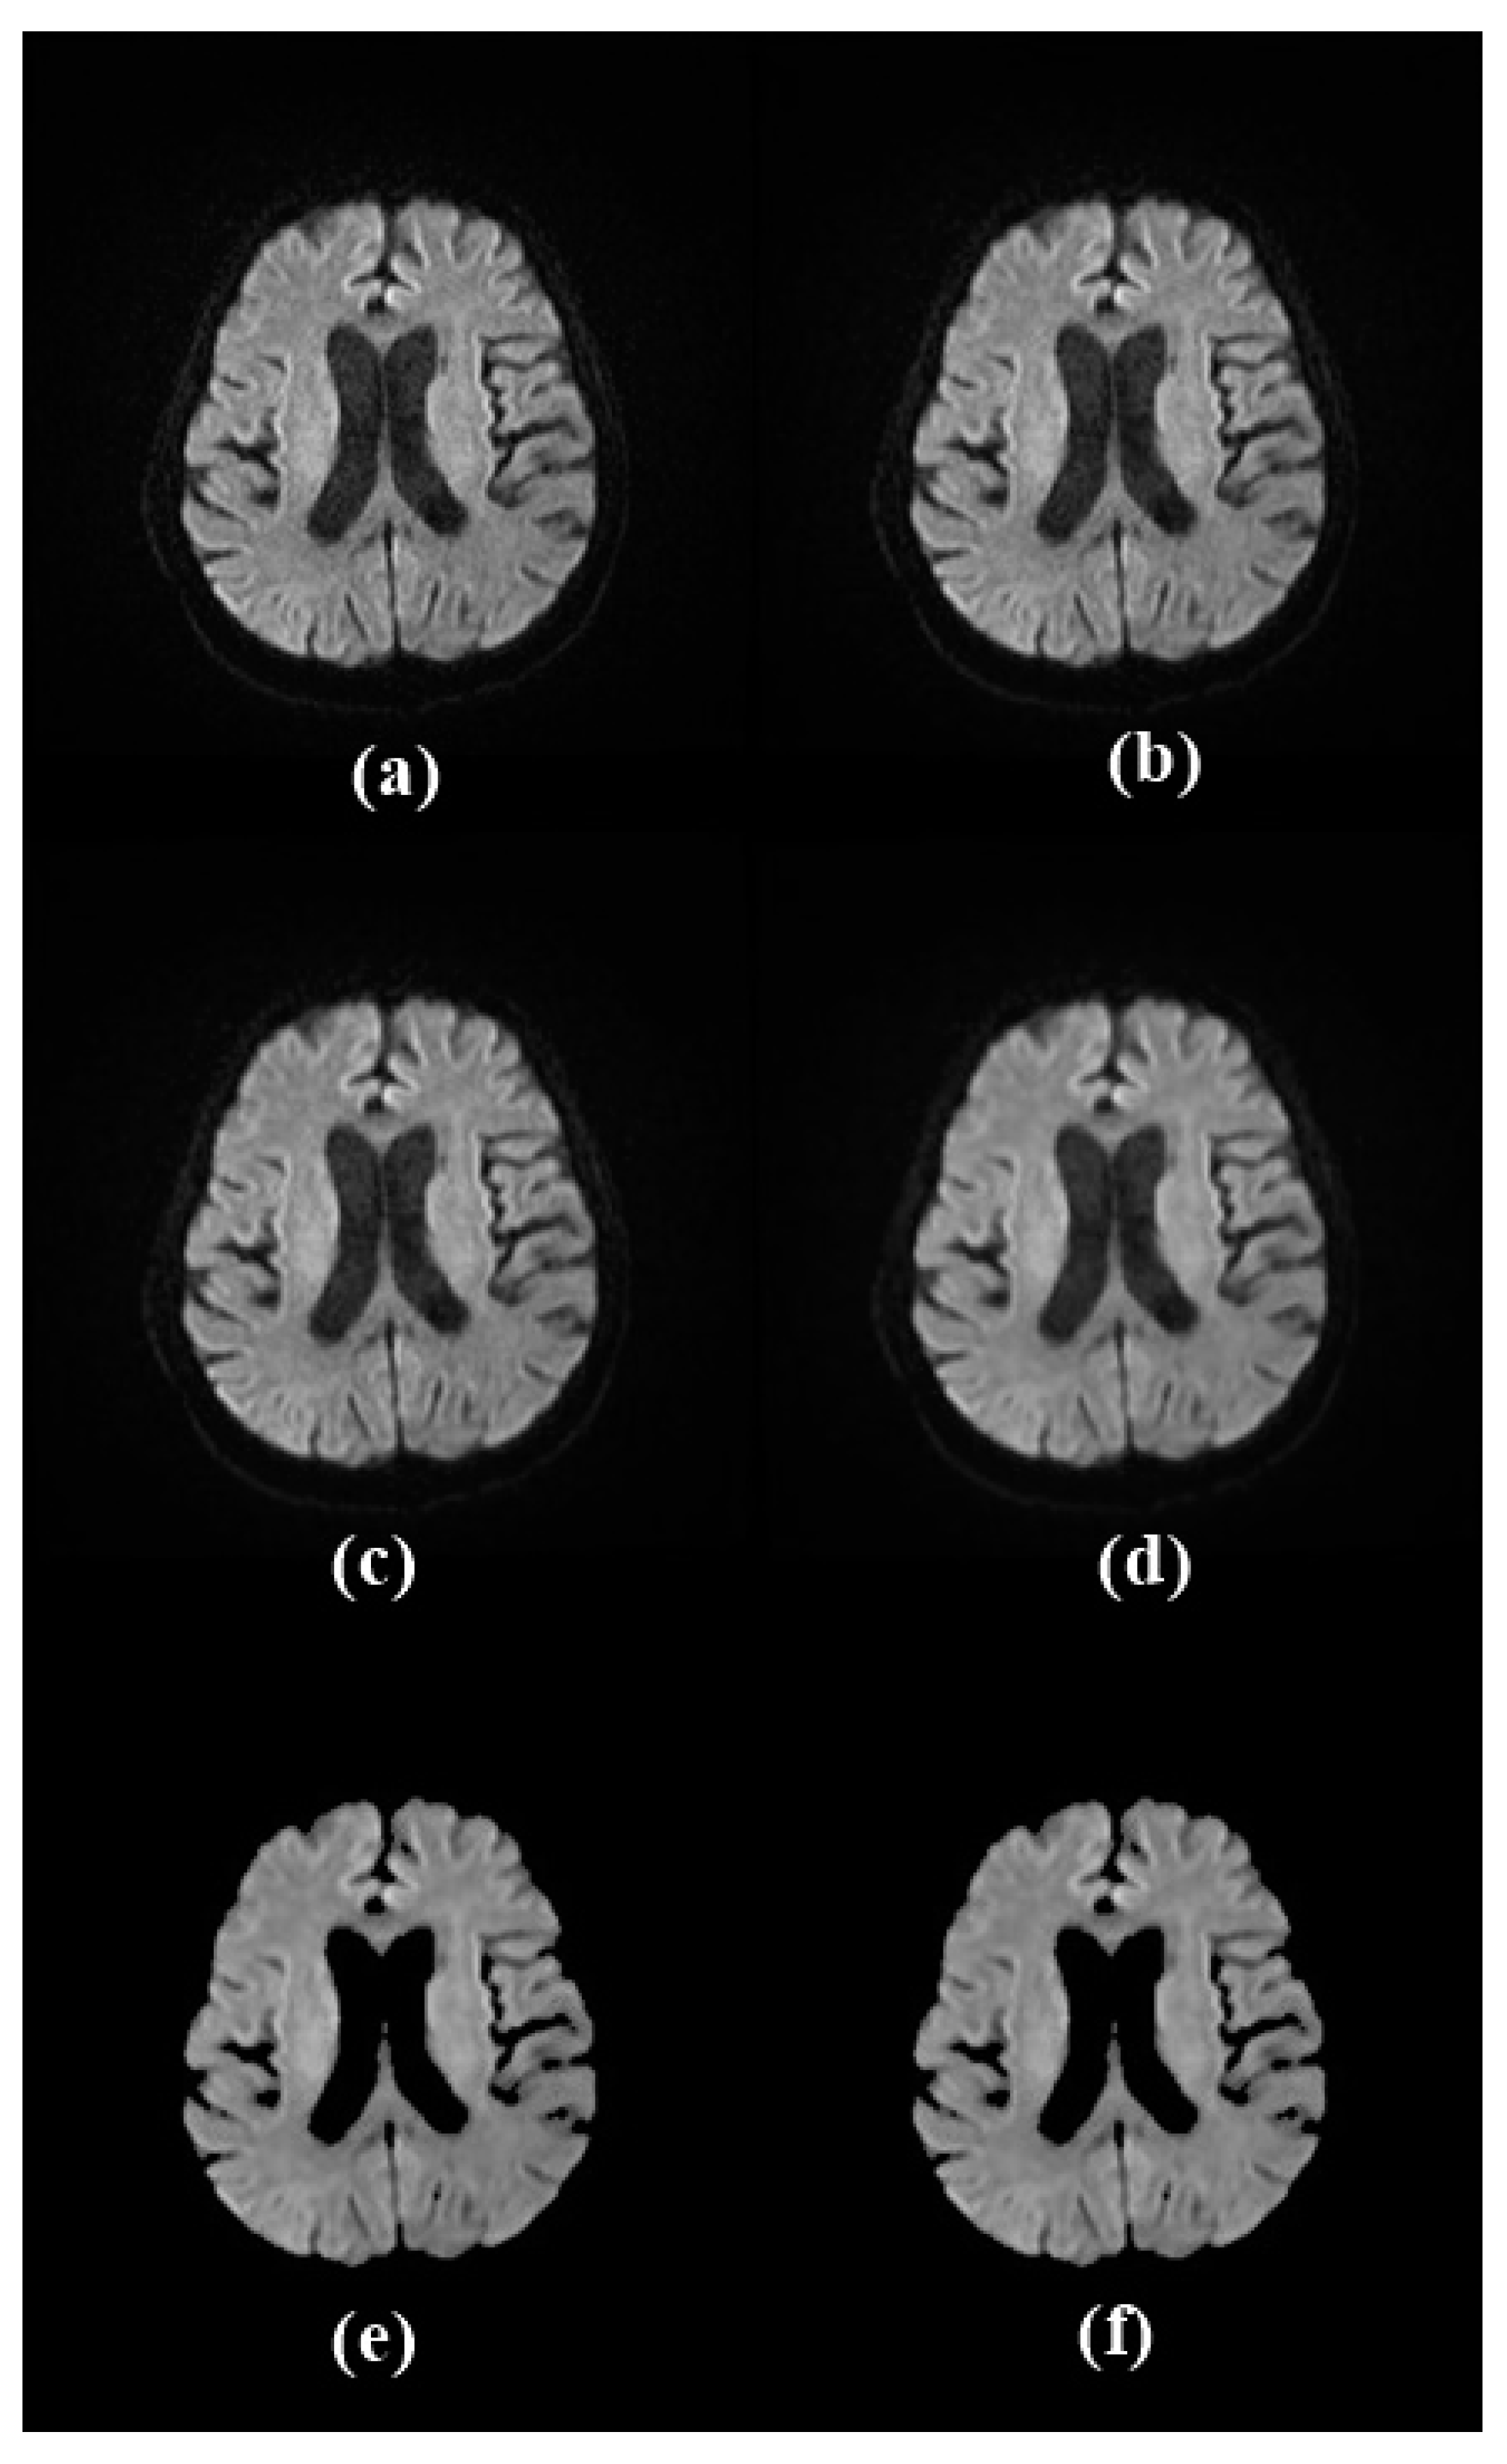

2.2.1. Image Preprocessing